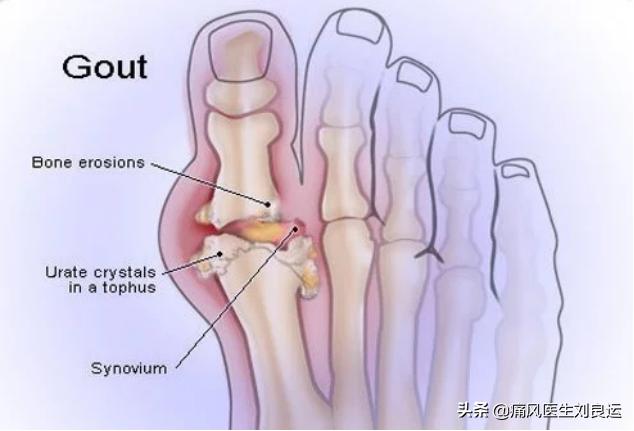

也有患者,却连自己所患疾病是不是痛风都不知道。虽然痛风起病是以第一跖趾关节和趾间关节疼痛剧烈难忍、肿胀和局部发红发热为主,但并非脚痛就非要确认为痛风,也并非脚不痛就不是痛风。今天我就来讲一讲,痛风容易被误诊的六种情况。

- 痛风引起的脚痛:常常是因为长期尿酸高于420μmol/L,因为过量进食、过量饮酒、过量摄取嘌呤和蛋白质、持续工作、持续熬夜、人际关系出现问题、进行激烈运动、运动导致出汗又未能及时补水、穿比较紧的鞋走路等,诱发脚的大拇趾关节红、肿、热、痛,常常发病是在没有任何先兆的夜晚或凌晨关节剧痛而惊醒,在24~48小时内疼痛就会达到高峰,一般有60~70%左右的患者首发于脚的大拇趾关节。

从前面我们可以看到,急性痛风性关节炎虽然大多发生在下肢关节,其中又以第一跖趾关节最为常见,全身其他各个关节均可受累。但是,脚痛并不一定就是痛风;痛风也不一定就只会发生在脚部。

这是因为,持续高尿酸值的状态后,虽然尿酸结晶可能沉淀在身体的每一个关节,但是容易沉积尿酸的关节不只是在脚部。只是痛风容易在脚的拇指关节发作而已,原因在于:脚趾处于肢体末端,血液循环相对较差,而且脚部温度相对较低;另外我们每天都要走路运动,容易导致脚部负担较大的压力,包括支撑体重、保持身体平衡等作用;此外脚部容易沉积尿酸盐结晶,而且体液酸碱值容易偏低,乳酸等代谢产物容易堆积。

其实有些痛风患者,在早期急性痛风发作时,疼痛的症状也是不够典型,比如说仅仅表现为关节刺痛或关节麻木、异物感、僵硬感等关节不适的感觉。因为这些不够典型的症状,也没有当作一回事,直到发展到关节畸形或出现典型的痛风影像学改变时才得以明确诊断。

- 常见临床症状诊断:如果符合下述标准的5条或以上即诊断为痛风:①急性关节炎发作>1次;②炎症反应在24小时内到达高峰,14天以内症状缓解;③单关节炎发作;④肉眼可见炎症发作关节发红;⑤第一跖趾关节疼痛或肿胀;⑥单侧第一纸质关节受累;⑦单侧跗骨关节受累;⑧可疑痛风石;⑨高尿酸血症;⑩不对称关节内肿胀。

- 关节滑液检查:急性痛风性关节炎患者的关节滑液增多,抽取滑液可见外观多为白色不透明的液体,在偏振光显微镜下可于白细胞内见到双折光的针状尿酸盐晶体。

- 肌骨超声检查:肌骨超声检查可以识别关节滑膜炎及积液、肌腱炎和腱鞘炎、滑囊炎、皮肤及皮下组织改变等,可以显示软组织、软骨、关节及痛风沉积物。